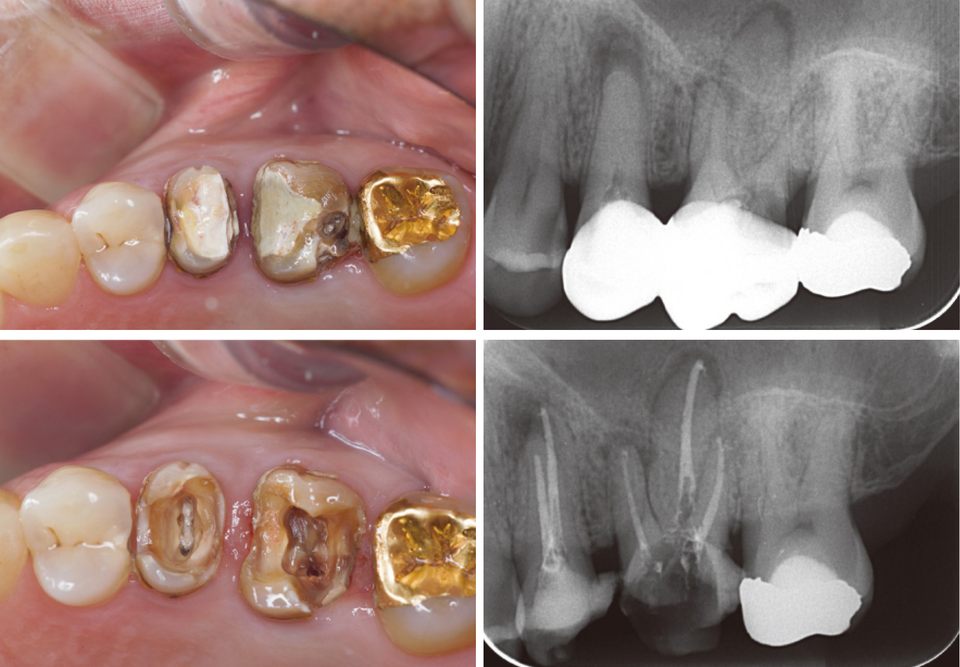

#14~#16 레진 충전

왜 이런 과정을 사진으로 기록할까? 개원한 치과의사는 누구의 간섭도 받지 않고 자신의 양심과 임상능력을 따라 진료한다. 임상 과정을 사진으로 기록하고 정리하는 과정에서 자신의 부족한 점이 드러난다. 최종 치료결과가 좋을 때는 자신감과 직업적인 보람을 얻기도 한다.